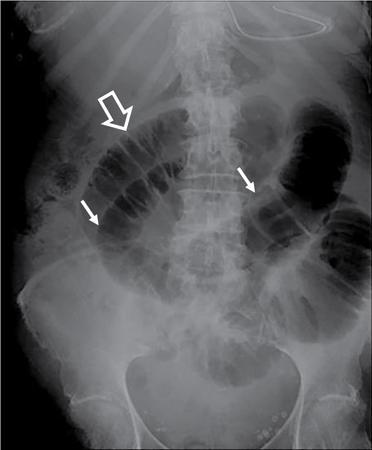

UNDERSTANDING THE ADULT ABDOMINAL RADIOGRAPH: TECHNIQUES AND INTERPRETATION Tanvi Modi Radiography of the abdomen is a common practice for the evaluation of abdominal organs. The anatomy and pathology of digestive, hepatobiliary and genitourinary systems can be assessed using radiographs, either as a stand-alone practice or as a primary imaging modality followed by contrast studies, ultrasound or cross-sectional imaging. In addition, abnormalities of the musculoskeletal or integumentary system can also be deduced on the basis of abdominal radiographs. This chapter intends to give an overview on the techniques and positioning in abdominal radiography as well as interpretation of normal and abnormal features. While superior imaging modalities such as ultrasound, computed tomography (CT), magnetic resonance imaging, capsule endoscopy and the likes have taken over abdominal imaging by and large, radiography still holds a pivotal role in certain situations and conditions, such as: The standard abdominal radiograph is taken in supine position and anteroposterior projection. This is also popularly known as the KUB (kidneys-ureters-bladder) radiograph. Previously, supine as well as erect radiographs were performed in all patients; however, this is not commonly done due to high-radiation dose. For all indications of abdominal radiography, including acute abdomen, supine radiographs are sufficient in terms of radiographic diagnosis, with the exception of perforation for which an erect chest or lateral decubitus radiograph can be performed if there is clinical suspicion. Patient should lie supine on the imaging table with median sagittal plane at right angles to the table and coincident with the midline of the table (Fig. 7.1.1.1). The body is divided into equal right and left halves by the median sagittal which passes through the sagittal suture of the skull. Pelvis should be adjusted so that the anterior superior iliac spines are equidistant from the table top. Gonadal shields, in the case of male patients, should be placed with the upper edge of the shield at the level of pubic symphysis. Although rarely used for female patients, these should be positioned between the anterior superior iliac spines and the pubic symphysis. The centre point of the image receptor should be approximately located at a point 1 cm below the line joining the iliac crests. The X-ray beam should be in a vertical direction, perpendicular to the table top and image receptor at the centre point. Collimation should be such that the soft tissue and subcutaneous region along lateral aspects of the abdominal cavity should be covered within the image. Also, the superior extent involving diaphragm and inferior extent involving the inferior pubic rami is important to look for any lower chest pathologies or any inguinal hernia. 35 × 43 cm (14 × 17 inches) in portrait orientation. On an average, abdominal radiograph exposes a patient to a dose of approximately 1.5 mSv, which is equivalent to 75 chest radiographs or 1/6th dose of a standard CT of the abdomen. The entrance skin dose is approximated to be 4 mGy. At such an effective dose, the additional lifetime risk of fatal cancer is 1 in 30,000. The exposure time is kept short. Patient is asked to exhale completely and hold their breath, with exposure taken at this point of full expiration to ensure imaging of abdominal organs in their natural positions. Modifications of this technique can be made depending on patient habitus and clinical condition. Kilovoltage peak (kVp) should be set to allow adequate visualization of abdominal soft tissue structures as well as semiopaque renal and biliary calculi. Average kVp is set at 70–85 kV. 102 cm (40 inches) Grids are commonly used to reduce scatter radiation. Placement of side marker on the image receptor at the time of radiographic exposure is essential. Bowel pattern depiction should be such that there is minimal lack of sharpness. Standard guidelines for abdominal radiography dictate that the radiograph should extend from the diaphragm up to the level of inferior pubic rami and must include the lateral abdominal wall musculature. The abdomen is divided into four quadrants on the basis of two perpendicular lines (Fig. 7.1.1.7). The vertical line passes through the mid sagittal plane and crosses the umbilicus and symphysis pubis. The horizontal line is a transverse line across the umbilicus at 90 degrees to the vertical line and is situated at the level of L4–L5 intervertebral disc. The quadrants are as follows: Another division system is dividing the abdominopelvic cavity into nine regions using two vertical and two horizontal planes (Fig. 7.1.1.8). The vertical planes, also known as the right and left lateral planes, are parallel to the midsagittal plane between midline and anterosuperior iliac spines on either side. Of the two horizontal planes, the upper transpyloric plane is at the level of lower border of L1 and the lower transtubercular plane is at the level of L5. The nine regions are: On a standard radiograph, the exposure should be such that the stomach, bowel loops, outlines of liver, spleen, kidneys, psoas muscles should be well identified. Also, lumbar transverse processes should be seen. Arch of the pubic symphysis should be visible to evaluate bladder region. A well-centred film without rotation will demonstrate bilaterally symmetrical lower ribs, iliac wings, ischial spines and obturator foramina. Different structures seen on an abdominal radiograph can be classified into five basic densities: Identification of different structures depends on the relative degree of contrast between their densities. The demarcation is clearer in chest and is diminished in abdomen due to relative similar soft tissue density of various structures. On a normal radiograph, relatively large amounts of gas in stomach and colon with minimal small bowel gas can be seen. Further, colonic gas can vary from negligible to extensive, mimicking obstruction pattern; however, usually the gas is enough to delineate colonic haustral pattern. Faecal matter gives a mottled appearance to colonic gas. Short-air fluid levels on an erect radiograph may be seen even in normal cases. The normal appearance of small bowel loops on an abdominal radiograph follows the rule of threes: Stomach is seen in the left upper quadrant and is visualized when distended with air. It is commonly seen extending from T11 to L2 level. Common feature identifying the stomach is the fundal gas which is usually seen as an air fluid level within the gastric lumen. Small bowel loops are distributed to the centre of the abdominal cavity and large bowel loops are peripheral. Duodenum is predominantly situated in right upper quadrant. It extends to left upper quadrant in the region of duodenojejunal flexure. Jejunum occupies the left upper and lower quadrants and is easily identified due to the presence of thick, numerous, closely spaced valvulae conniventes (Fig. 7.1.1.9A). The ileum occupies both lower quadrants and extends into right upper quadrant. Ileum has few and less prominent valvulae as compared to jejunum (Fig. 7.1.1.9B). Ascending and descending colon are retroperitoneal and have relatively fixed positions along lateral aspect of the abdominal cavity on either side. Transverse and sigmoid colon, on the other hand, may have a variable position due to their mobility along mesocolon and redundant pattern. These can be identified with confidence on account of haustrations and faecal matter (Fig. 7.1.1.10). Haustrations are usually well seen in ascending and transverse colon and poorly delineated beyond splenic flexure. Caecum is in the right lower quadrant, though it may be mobile or pulled up. Rectal gas is usually seen in the midline at the level of pelvis and its presence rules out large bowel obstruction. All these positions may vary due to anatomical conditions such as malrotation or pathological conditions, for example volvulus. Liver, spleen and renal outlines cannot be completely traced with precision due to the overlap by bowel loops. On a frontal projection, the liver appears as a triangular structure occupying right and left hypochondrium and epigastric region. Occasionally, the right lobe may be seen extending lower than the right renal shadow. This is a normal variant known as Reidel’s lobe. Gall bladder is situated in the posterior and inferior region of the liver and any pathology of the gall bladder should be looked for in this region. On a lateral radiograph, the gall bladder is anterior to the midcoronal plane. This helps in distinguishing gall bladder calculi from renal calculi, which will be more posteriorly situated. Spleen is seen in left upper quadrant/left hypochondrium, flushed to left lower ribs and left hemidiaphragm. Pancreas is present in the epigastric region (right and left upper quadrants) and is usually not identified in the absence of a pathology. The kidneys are bean-shaped retroperitoneal organs which are seen on either side of the vertebral column and lateral to psoas muscles. Due to the presence of liver on the right side, this kidney is slightly lower in position as compared to its contralateral counterpart. The visualization of kidneys on radiographs is facilitated by the surrounding fatty capsule. Kidneys lie between T11–12 and L2 level, with left kidney 1 cm higher than the right. Psoas muscle shadow can be normally seen along lateral aspect of lumbar spine bilaterally and is mildly concave (Fig. 7.1.1.11). Abdominal wall muscles are not routinely assessed on radiography; however, inclusion of lateral abdominal wall (muscles as well as subcutaneous plane) is a must while performing radiography. The flank stripe or the properitoneal fat stripe is a fat density linear concavity seen along lateral abdominal wall (Fig. 7.1.1.11). It is bound by the paracolic gutters and air-filled ascending and descending colon. All the solid organs in the abdomen are identified due to the fat density outlining them. Distortion of these fat lines helps in identifying organomegaly or focal mass lesions. The dome of urinary bladder is outlined by fat, which aids in differentiating its density from other soft tissue structures of the pelvis. Not all calcifications seen on abdominal radiograph are abnormal. Some may depict age-related changes such as vascular calcifications involving abdominal aorta, pelvic vessels, splenic artery in the region of left upper quadrant. Within the pelvis, phleboliths may be seen and mistaken for urinary calculi. Assessment of lumbosacral spine, iliac bones and femoral heads can be made on the basis of plain radiography. Degenerative changes may be commonly seen. Lower ribs can also be evaluated for pathologies. Dilated small bowel loops with rounded soft tissue density in midline over umbilical region suggests obstruction secondary to umbilical hernia. Pneumoperitoneum must be looked for in all cases of acute abdomen. While erect chest and left lateral decubitus radiographs can detect even 1 mL of free air, there are multiple signs on supine radiograph to suggest this diagnosis, for example Rigler’s sign, falciform ligament sign, football sign (Figs. 7.1.1.24 and 7.1.1.25). Retroperitoneal perforation may demonstrate air outlining psoas muscles and retroperitoneal organs. Small amount of free air may persist in the abdominal cavity up to 3 weeks after surgery, although it usually resolves within a week. Clinical history is important in such cases. Air foci within the bowel wall may represent bowel ischaemia/strangulation. Linear gas patterns in right hypochondrium may be due to two causes, that is pneumobilia and pneumoporta. The former can be seen normally postbiliary surgery, sphincterotomy, ERCP or in the case of abnormal fistulous communication between bowel and biliary tree (Fig. 7.1.1.26A). Pneumoporta (Fig. 7.1.1.26B) is a red flag and warrants further investigation to look for conditions such as mesenteric ischaemia and toxic megacolon. Pneumobilia is more centrally located whereas air shadows in pneumoporta are seen reaching up to periphery of liver. Air foci over renal shadows (Fig. 7.1.1.27), gall bladder or pancreas, in the absence of recent procedural history, suggest fulminant infection and mandate urgent intervention. Central midline calcific foci between T9 and T12 vertebrae can be attributed to calcific pancreatitis (Fig. 7.1.1.28). In the left upper quadrant, areas of calcification seen involving a shrunken spleen may be seen in autosplenectomy. In right upper quadrant, calcified gall stones may be seen. These tend to be small, multiple, uniformly circumscribed and ring-like in appearance with central translucency (Fig. 7.1.1.29A). Mercedes Benz sign, a triradiate pattern of gas lucency, is associated with gallstones. In contrast, renal calculi are more commonly solitary, irregular, of homogenous density, conform to renal calyceal or pelvic outline (Fig. 7.1.1.29B) and are sometimes of staghorn configuration. On lateral view, the gall stones are more anteriorly located as compared to renal calculi, which may be partly superimposed on lumbar vertebrae. Ureteric calculi tend to overlap bony structures such as lumbar transverse processes (Fig. 7.1.1.29B) or sacroiliac joints. Extensive or patchy, curvilinear calcification of gall bladder wall is known as porcelain gall bladder which is often associated with malignant transformation. Calcification involving adrenal glands may be secondary to infection or haematoma, or a congenital condition known as Wolman’s disease where there is bilateral involvement. Discontinuous discrete midline tram track calcification in the abdomen may indicate atherosclerotic changes in abdominal aorta and branch vessels. However, when the calcification is in a globular pattern and seen below the level of L2 vertebra, aortic aneurysm should be suspected (Fig. 7.1.1.30). Appendicoliths, though not commonly seen, may sometimes be detected in right iliac region. Pelvic calcifications: vesical calculi, distal ureteric or vesicoureteric junction calculi, calcified fibroids, ovarian dermoid with tooth-like calcifications (Fig. 7.1.1.31) may be the cause of abdominal pain and should be diligently looked for. Vesical calculi are usually more large and central in location whereas calcification due to fibroids may be more lateral. Schistosomiasis is another cause of bladder wall calcification, as is calcification of bladder tumours. Phleboliths tend to be bilaterally symmetrical, with a lucent centre unlike ureteric calculi. While it is believed that phleboliths are located below the level of ischial spines and ureteric calculi above, this is not always true and should be confirmed with CT. Fluid may collect adjacent to properitoneal fat line, forming a linear soft tissue density separating the fat line from the ascending or descending colon. Hellmer’s sign demonstrates medial displacement of lateral edge of liver (hepatic angle), due to fluid collection or ascites. Gross ascites may appear as generalized abdominal haziness or diffuse increased density of pelvis. Abscesses can involve any solid organ and in such cases may be difficult to demonstrate on plain radiography alone. Enlargement of organ or faint gas densities within can be suggestive of the same. In the case of peritoneal abscess, mottled density due to air, fluid and necrotic contents point towards this diagnosis, especially in right iliac fossa in association with appendicitis. Retroperitoneal abscess, similar to any retroperitoneal mass, may cause displacement of retroperitoneal structures (Fig. 7.1.1.32). Subdiaphragmatic abscesses may show concomitant ipsilateral pleural effusion (Fig. 7.1.1.33). These should be differentiated from Chilaiditi syndrome. Fluid and soft tissue lesions present with the same density on radiographs. While it is difficult to characterize the lesion and organ of origin, clues for the same can be provided by organomegaly (Fig. 7.1.1.34), distortion of fat surrounding solid organs, displacement of bowel loops or solid organs. For example, a retroperitoneal lesion may cause anterior or inferior displacement of kidney, a pelvic mass may cause upward displacement of small bowel loops. Different densities such as fat or calcification may help in identifying organ of origin (e.g. fat and tooth densities seen in ovarian dermoid). Convexity of margins of psoas muscle on an abdominal radiograph can be due to haematoma, abscess or intramuscular tumour. Radiographs are performed for the initial diagnosis of foreign body in the abdomen including type, number of foreign bodies, location, size and shape (Fig. 7.1.1.35). Radiolucent foreign bodies such as wood, plastic, chicken bones will not be easily identified on radiography. Low kVp (65–70 kVp) can increase contrast and help identify these objects. In addition to an abdominal radiograph, chest radiography is also performed to exclude aspiration or oesophageal location of foreign body. Ingested or introduced foreign bodies may cause complications such as obstruction, perforation, fistula formation and sepsis. Hence, once their presence is confirmed, follow up radiography must be performed until they are eliminated. One must look for fractures/dislocation injuries involving the vertebrae or pelvic bones, especially after history of trauma. Lucent expansile lesions or sclerotic bony deposits which represent neoplasms, absent pedicle sign in cases of metastasis, metabolic bony changes such as rugger jersey appearance, Paget’s disease, arthropathies such as ankylosing spondylitis with bamboo spine appearance and sacroiliitis (Fig. 7.1.1.36) are some of the conditions which may be diagnosed based on an abdominal radiograph. Overlap of bowel loops over iliac blades may lead to a misdiagnosis of lucent lesions and should be evaluated with caution. Basal pneumonia may be the cause of acute abdominal pain and should be looked for in abdominal radiography. Similarly, pleural effusion, pericardial effusion, calcified pleural plaques, achalasia, interstitial fibrosis are few other findings that can be seen in lower chest on an abdominal radiograph. Basilar atelectasis can give a deceptive appearance of pneumoperitoneum (Fig. 7.1.1.37). Surgical clips, commonly in right hypochondrium after cholecystectomy, drainage tubes, ventriculoperitoneal shunts, femoral line catheters, IVC filters, stents (vascular, renal, biliary) (Fig. 7.1.1.38), stoma bags, contraceptive devices are some structures that may be seen in an abdominal radiograph. Correct knowledge of patient history and normal locations of these structures prevents misdiagnosis. Certain artefacts may be projected upon the radiograph due to surface structures such as trouser buttons, body piercing, sequins over clothing and should not be considered as a pathology. Multiple skin surface nodules in cases of neurofibromatosis, soft tissue focal swellings, such as abscesses, lipomas, haematomas, desmoid tumours and malignant lesions may be incidentally seen on radiography. These can be further evaluated using ultrasound or CT. Subcutaneous emphysema is another finding that may be seen in lower abdominal wall secondary to retroperitoneal perforation or diffusely along abdominal wall in the case of bowel perforation (Fig. 7.1.1.39). Foreign bodies such as bullets and pins may be seen lodged in abdominal wall. A systematic approach to abdominal radiographs is important for accurate diagnosis as follows: Despite the development of newer techniques for imaging of the abdomen, plain radiography still holds an important place in the initial assessment of acute abdomen. Positive and negative findings on an abdominal radiograph can direct further investigation. Ideal positioning, recognition of normal appearances and keen scrutiny for pathologies is a sine qua non for radiologists reading a plain film of the abdomen. OESOPHAGOGRAM Padma V. Badhe, Vikram Reddy, Sultan Moinuddin Shaukatali, Zillani Alam, Ravi Varma, Abhishek Bairy, Dasari Ravikiran, Revati Tekwani, Soniya Patankar, Megha Nair, Gautham Shankar Oesophagogram is the process of obtaining radiological images and simultaneous motion recording to evaluate function and disorders of pharynx, oesophagus and proximal stomach. Oesophagogram is usually done primarily to evaluate dysphagia. Some of the common indications are oesophageal motility disorders, strictures, gastro-oesophageal reflux disease (GERD) and suspected masses. It can also be used to detect uncommon anomalies like vascular rings/slings and aberrant anatomy. It also helps to evaluate further in cases where there is inability to pass upper GI scope. Double-contrast oesophagogram is mainly indicated in early mucosal disease like erosion, polyp, infection and tumours. If a motility disorder is suspected, dynamic technique (e.g. videofluoroscopy) is used for dysphagia or aspirations in cases of stroke, neuromuscular disorders, post head and neck surgery or radiation. Barium oesophagogram is contraindicated in suspected cases of perforation and tracheoesophageal fistula, aspiration, rarely if there is hypersensitivity to barium suspensions. It is also contraindicated in suspected oesophageal perforation where a water-soluble contrast agent is more suitable. However, ionic water-soluble contrast agent is better avoided in cases of aspiration or fistula with airway. The contrast examination of the pharynx is dangerous in cases of acute epiglottitis and must be ruled out on plain radiograph. An 80% w/v barium suspension is used in full column views. However, 200%–250% w/v barium suspensions is usually required for mucosal relief films. The barium sulphate mixture is fed to the patient either by spoon, by glass, or through a drinking straw, depending on its consistency. In videofluoroscopy, the pharyngeal phase of swallowing is usually safer with barium pudding than with thick barium and safer with thick barium than with thin barium. However, if the major abnormality is poor pharyngeal contraction leading to stasis in the piriform sinus (and epiglottic tilt is normal), a thin liquid is safer. Epiglottic motility is better assessed with thin barium because thick barium often obscures the epiglottic tip. Fluoroscopic equipment capable of cine fluoroscopy and capability for rapid sequence spot images (high frame rate) is needed for this examination, Barium suspension, straw, glass, Lead apron and radiation protective equipment. The patients are instructed to fast after midnight before the day of the examination. The pharynx should be made as dry as possible during the examination as high-density barium adheres to dry pharyngeal mucosa. Activities like smoking, chewing gum and lozenges must be abstained before the procedure as they impair barium coating by increasing the salivary secretion. Regular oral medications must be taken with sips of water; however, insulin must be skipped on the morning of examination. The major principles of a good oesophagogram includes mucosal coating, distension and projection. A routine oesophagogram consists of screening of the oral, pharyngeal and oesophageal phases of swallowing, single and double-contrast examination of pharynx, single contrast, double-contrast and mucosal relief views of the oesophagus. In cases of dysphagia, the examination is tailored depending on whether the symptoms are either pharyngeal or oesophageal and initial fluoroscopic findings. If patients’ symptoms are suggestive of oral or pharyngeal disorder then pharynx is evaluated first. Similarly, if patient is suspected to have thoracic oesophageal disease then, double-contrast examination of the oesophagus is performed before the pharyngeal evaluation. During an oesophagogram the positioning of the patient varies according to the type of examination (Table 7.1.2.1).